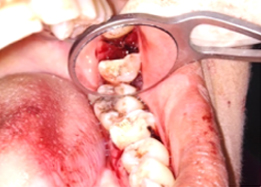

Post-OP Clinical View